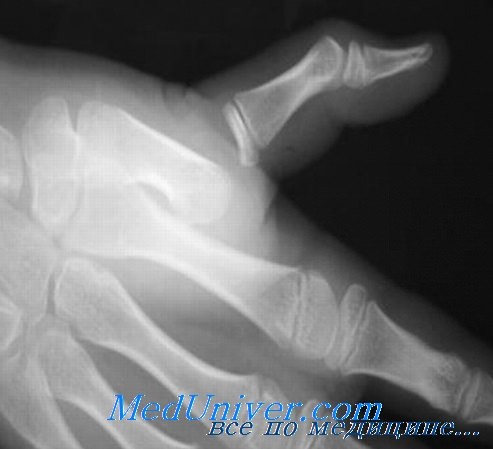

image а-в — различные виды вывихов в пястнофаланговом суставе большого пальца:

а) простой неполный вывих,

б) простой полный вывих,

в) полный вывих

г-д — вывих большого пальца правой кисти в пястнофаланговом суставе у пожилого больного наступил много лет тому назад. Вправление вывиха оказалось безуспешным, функция большого пальца была нарушена (а). Нарушение функции пальца усугублялось деформирующим артрозом, возникшим у больного за эти годы.

На рентгеновском снимке видно (б), что основная фаланга большого пальца вывихнулась к ладони.

В первом запястно-пястном суставе обнаруживается тяжелая, а в остальных суставах умеренная форма деформирующего артроза